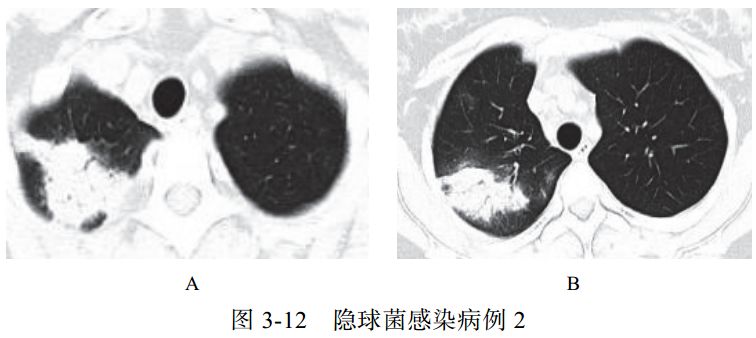

病例展示

图片